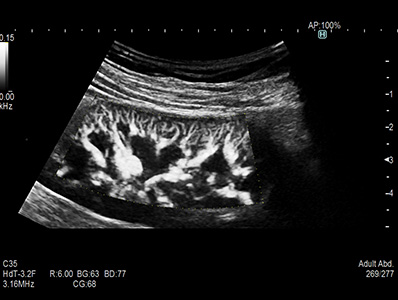

Use of trapezoid mode with a linear transducer extends the width of the field of view permitting a greater understanding of the orientation and size of the target and its surroundings.